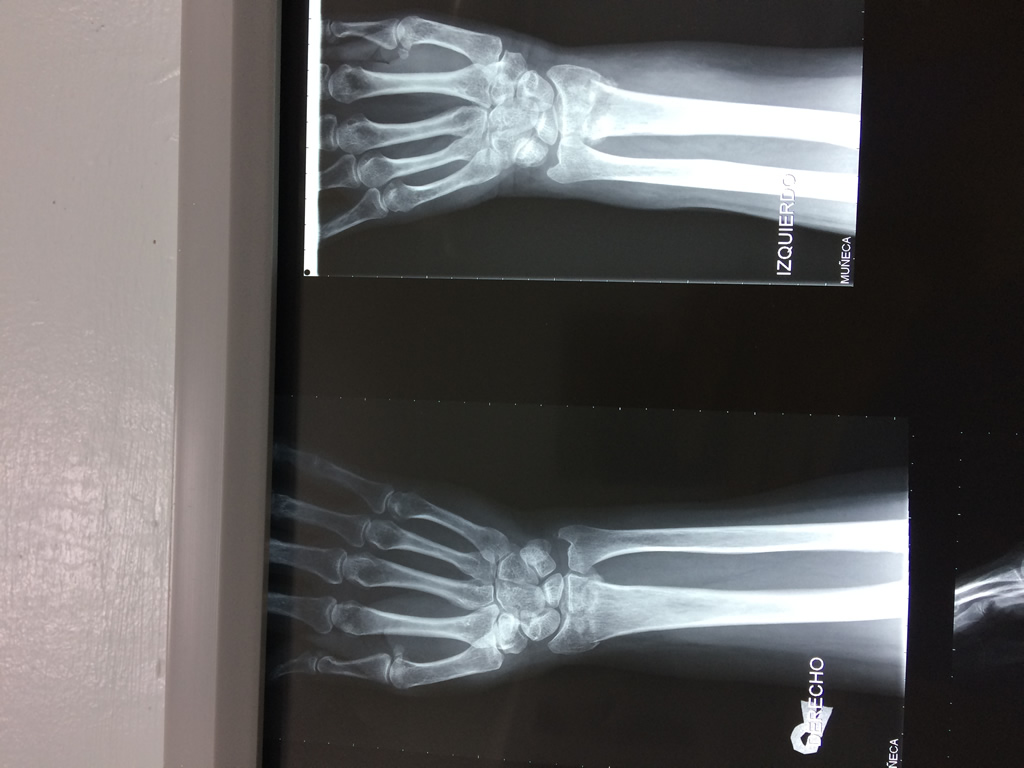

Cirugías de Húmero - Cirugías de Muñecas y Manos

Los procedimientos más comunes en cirugía de la mano son aquellos destinados a reparar traumatismos, incluyendo lesiones de tendones, nervios, vasos sanguíneos, y articulaciones; huesos fracturados; y quemaduras, cortes, y otros daños de la piel.